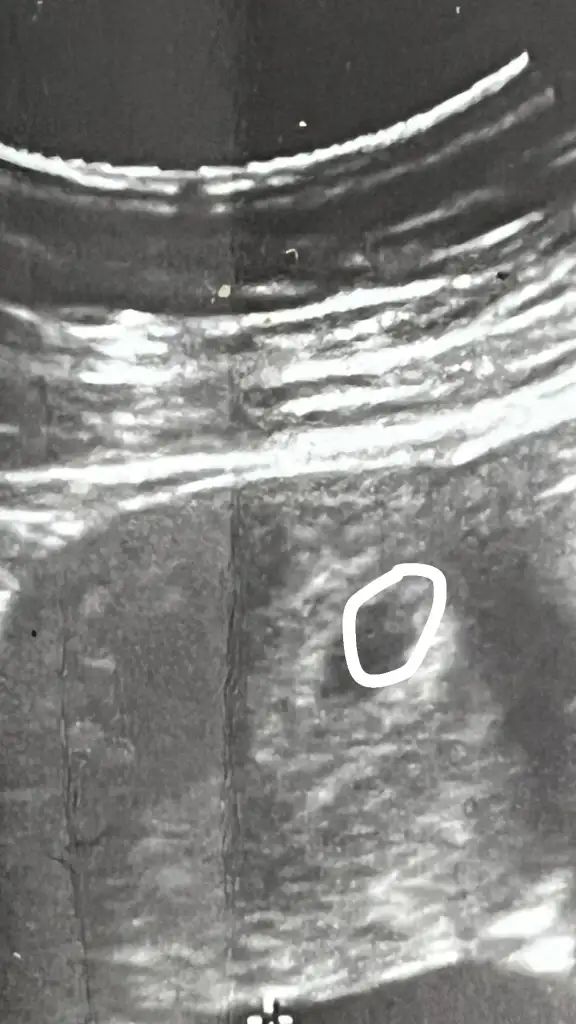

Yolk sac mı bu çizdiğim yer?

yolk sac mı?